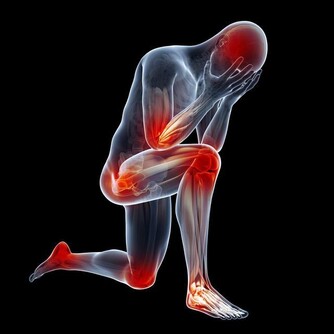

腎病

1.整個面色黎黑垢濁,下眼瞼腫,色黑,為腎久病。

2.下發暗紅色。

14. 下巴是腎和全身有酸痛的地方;也叫疲勞酸痛區。

15. 整個下巴到耳朵包括耳朵為腎區。